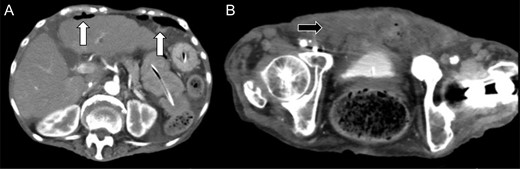

We reviewed the abdominal CT on admission, which revealed a deficit in the urinary bladder wall, with fluid collection around it (Fig. 3). The perforation of the urinary bladder was present on admission, and that of the peritoneum occurred on the following day. Previous magnetic resonance imaging revealed no diverticulum of the urinary bladder or any organic failure.

Review of the enhanced abdominal computed tomography on admission after the operation revealed (A) fluid collection in the posterior space of the urinary bladder (black arrow) and (B and C) deficit in the urinary bladder wall and suspected perforation (white arrow).